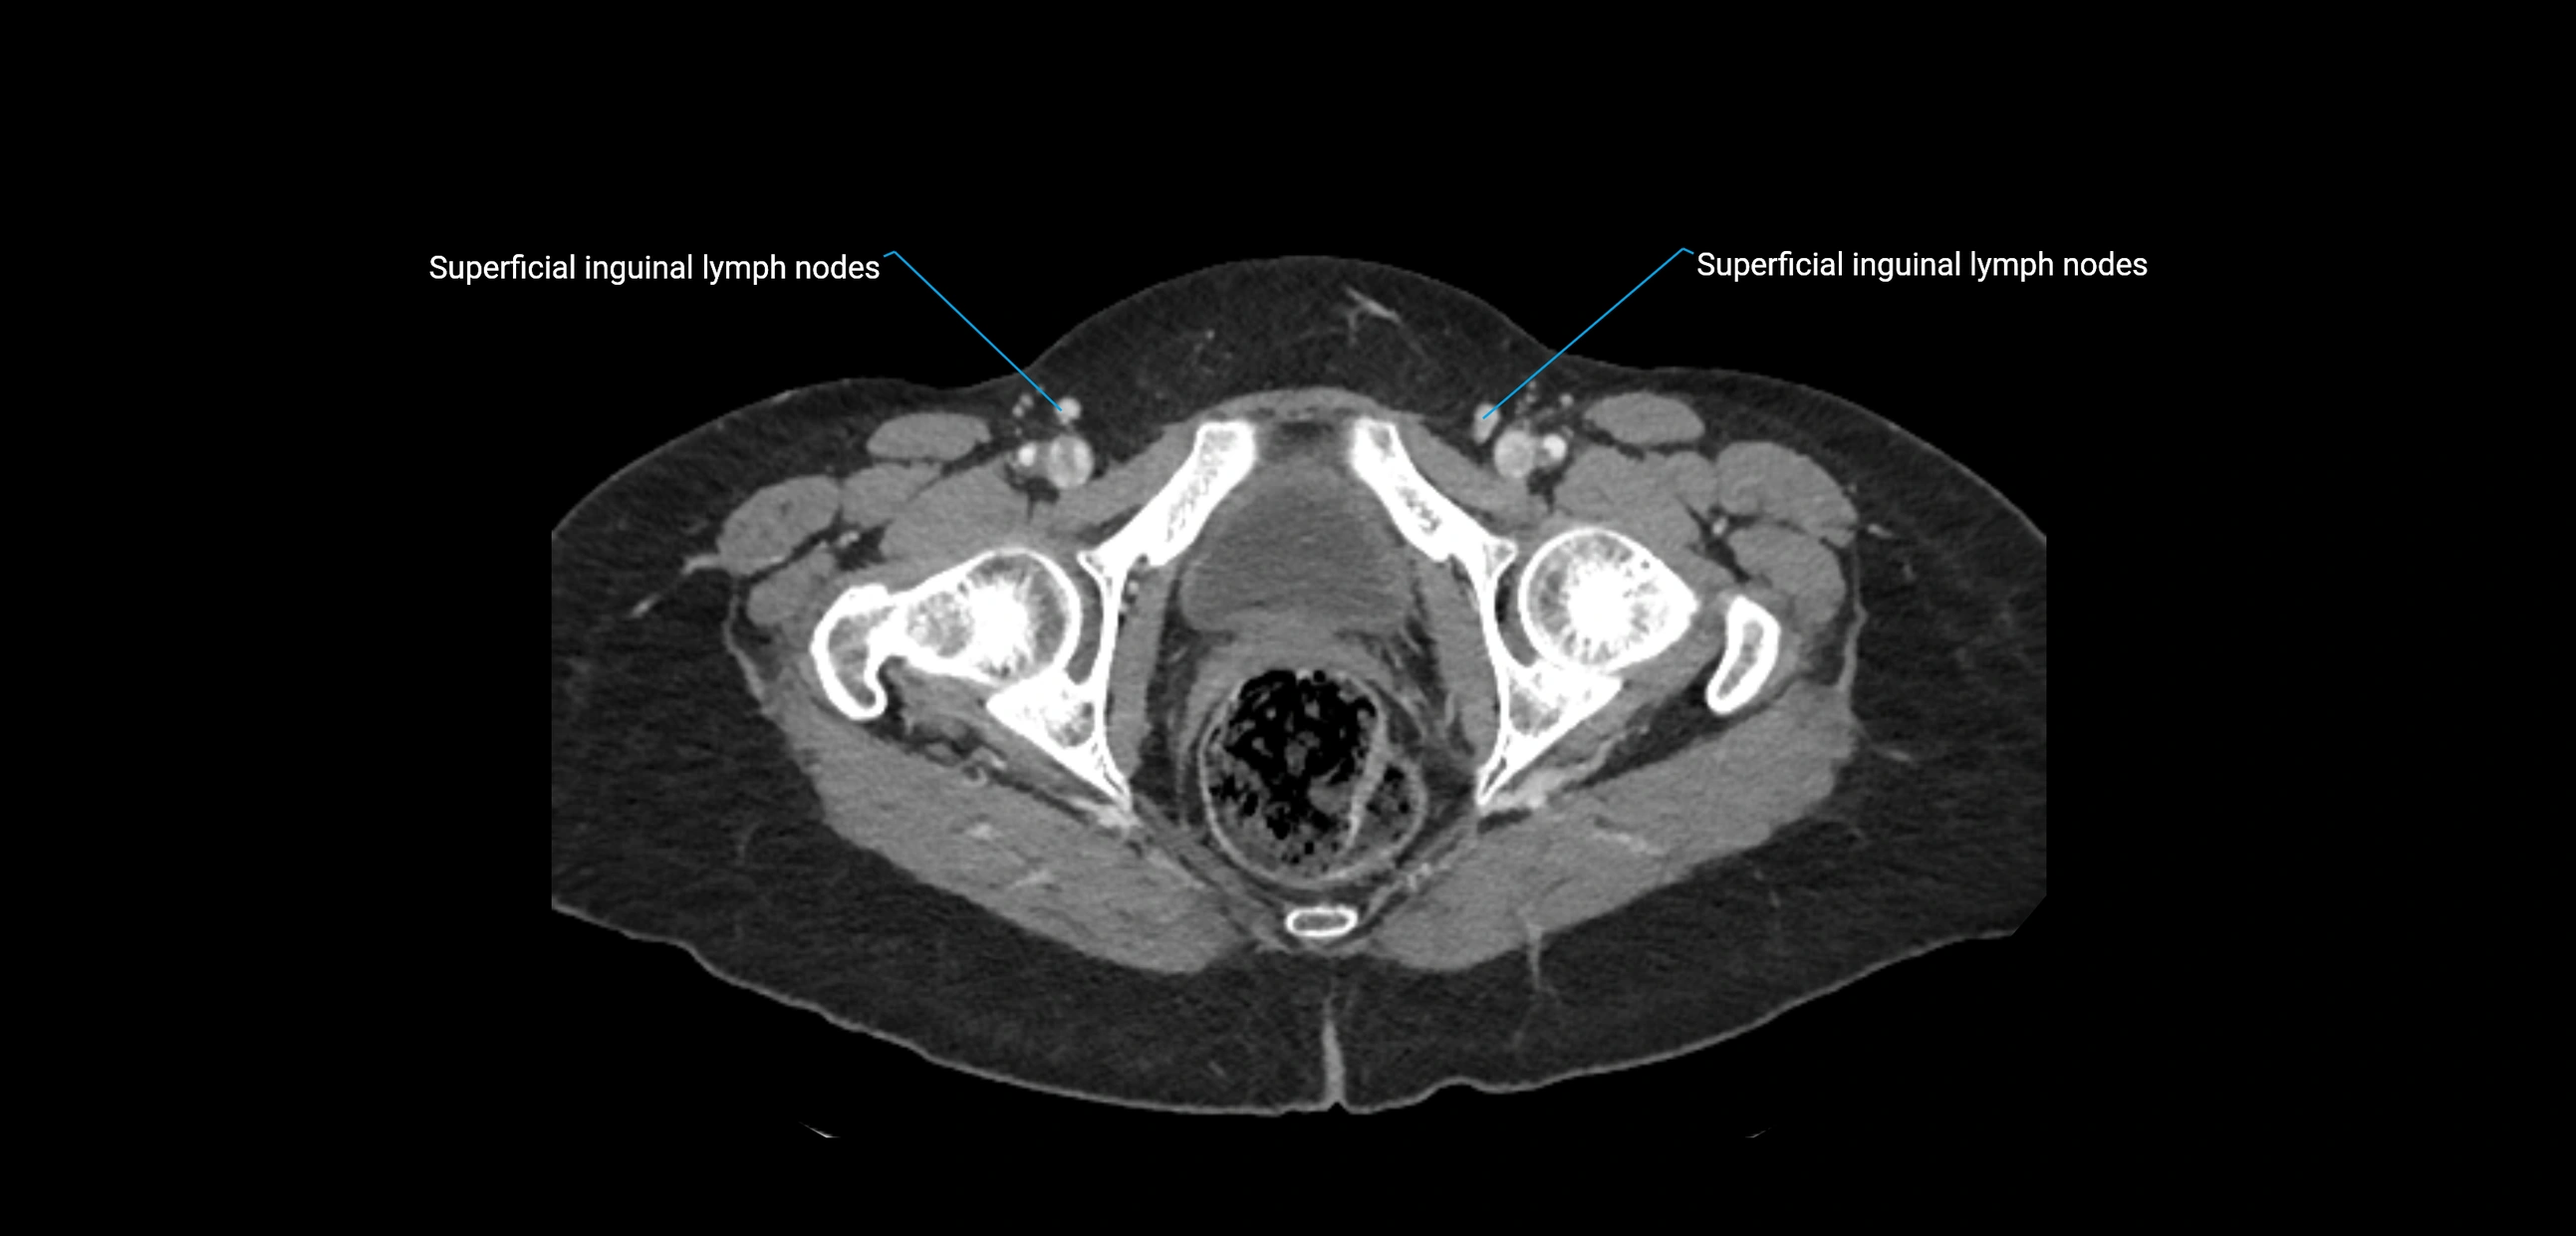

CT image

image